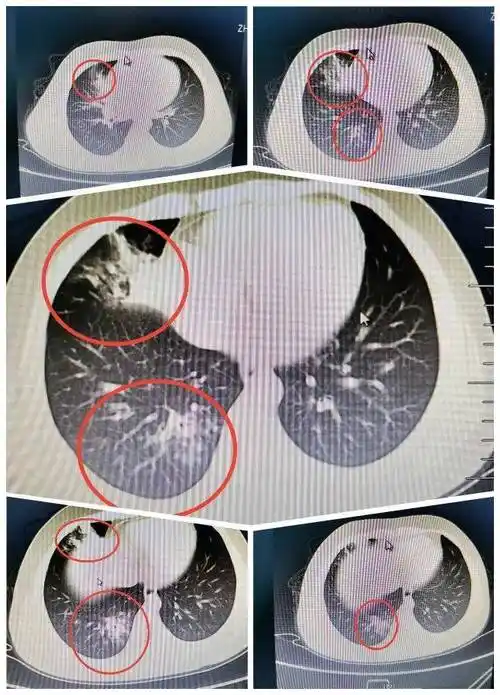

小儿推拿杨晓:儿童大叶性肺炎来势凶猛,家长如何识别,预防护理_患儿